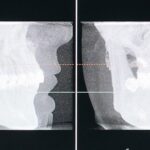

Dental X-Rays

Understanding TMJ Disorders: Symptoms, Issues & Treatment